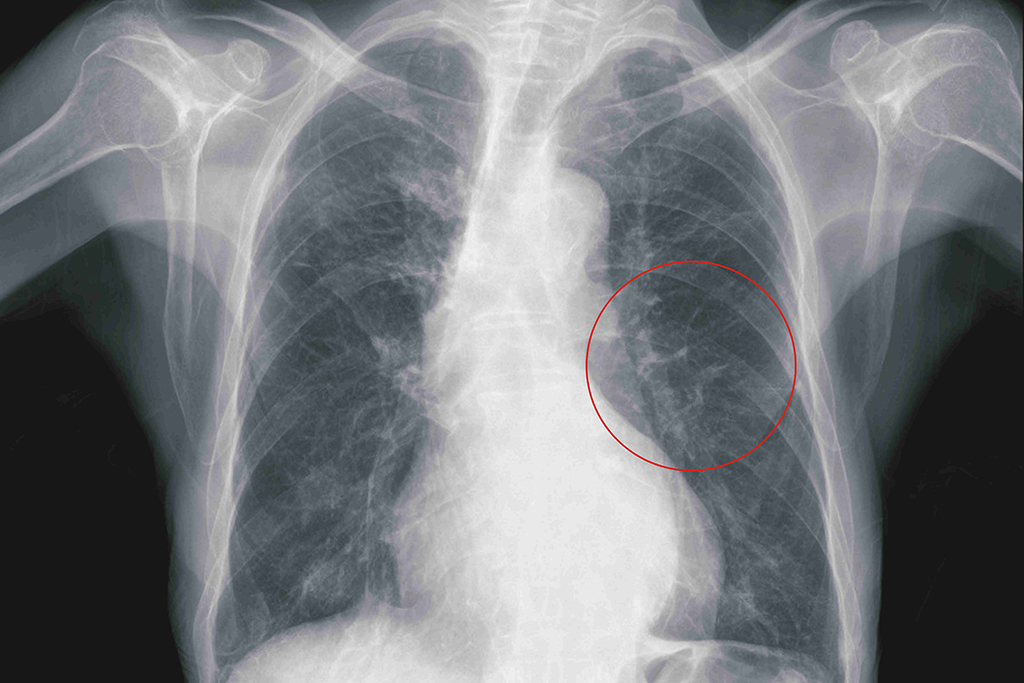

鄭雅夫醫師指出,一位52歲男性為因為罹患下咽癌合併多處轉移,經過化療及免疫治療後,仍然有右上肺及右下肺的腫瘤存在。患者於7個月前接受胸腔鏡右上肺及右下肺部分切除後腫瘤控制較穩定。此次再次發現右下肺長出一顆三公分的腫瘤,有鑑於病患的肺功能不佳,二次手術也容易沾黏較不合適,於是選擇了在複合式手術室中做微波肺部消融術治療,術後腫瘤消融狀況良好,病患也於觀察一天後即可出院,肺部消融術是一項針對不適合接受肺部切除術的良好替代選擇。

52歲男性患者,微波消融術前,右下肺一顆3公分腫瘤。

52歲男性患者,腫瘤經微波消融術而壞死。